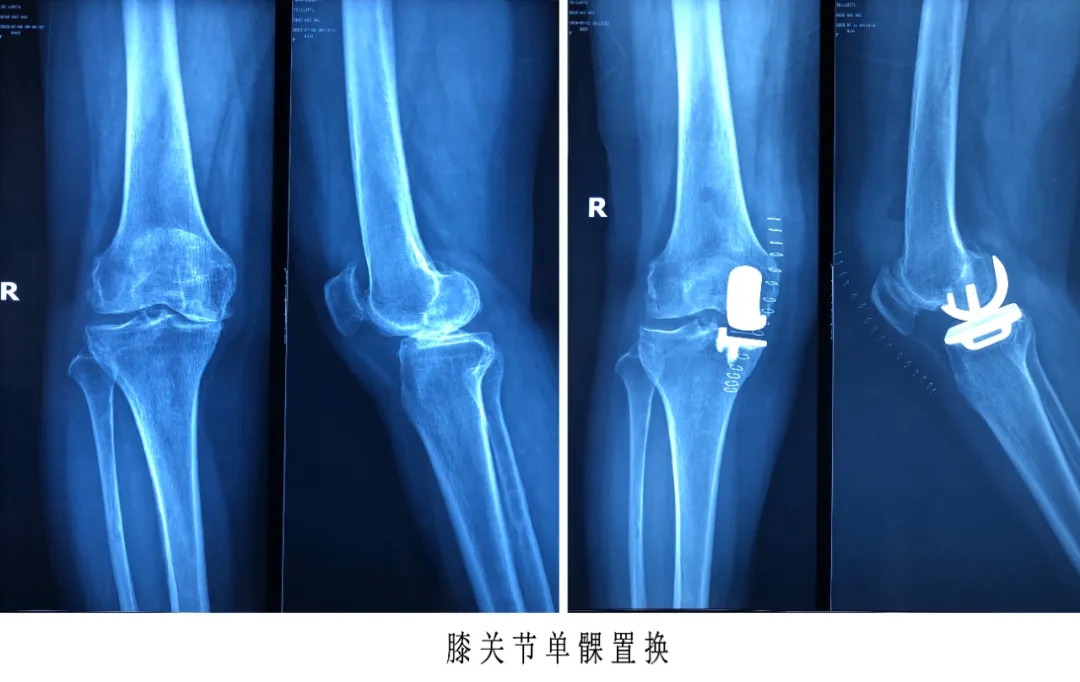

膝关节单髁置换术:

膝关节单髁置换术是一种微创手术,通过手术治疗可以快速恢复膝关节功能,术后疗效非常理想。由于手术时保存了患者的膝关节内全部韧带,手术过后膝关节的活动范围较大,而且步态接近于正常,能够正常下蹲及上下楼梯。